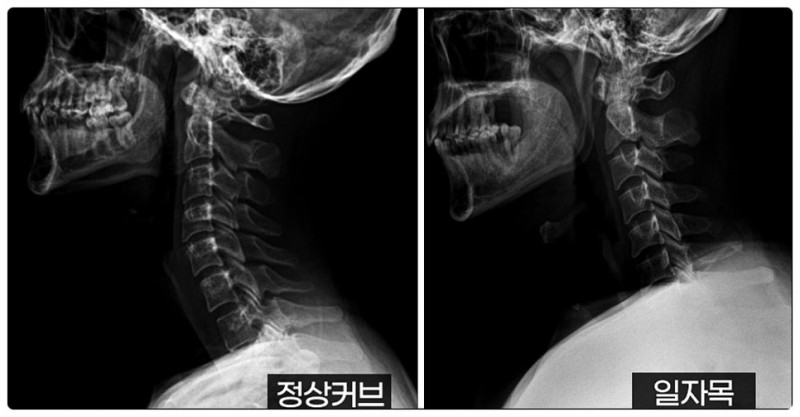

경추, 즉 목뼈는 원래 완만한 C자 곡선을 가지고 있습니다.

이 곡선은 자동차 서스펜션처럼 충격을 흡수하는 역할을 하지요.

그런데 교정이 필요한 경우, 이 곡선이 사라지면서 충격 완화 능력이 떨어집니다.

결과적으로 디스크가 지속적으로 압박을 받으며 목디스크나 퇴행성 질환으로 이어질 수 있습니다.